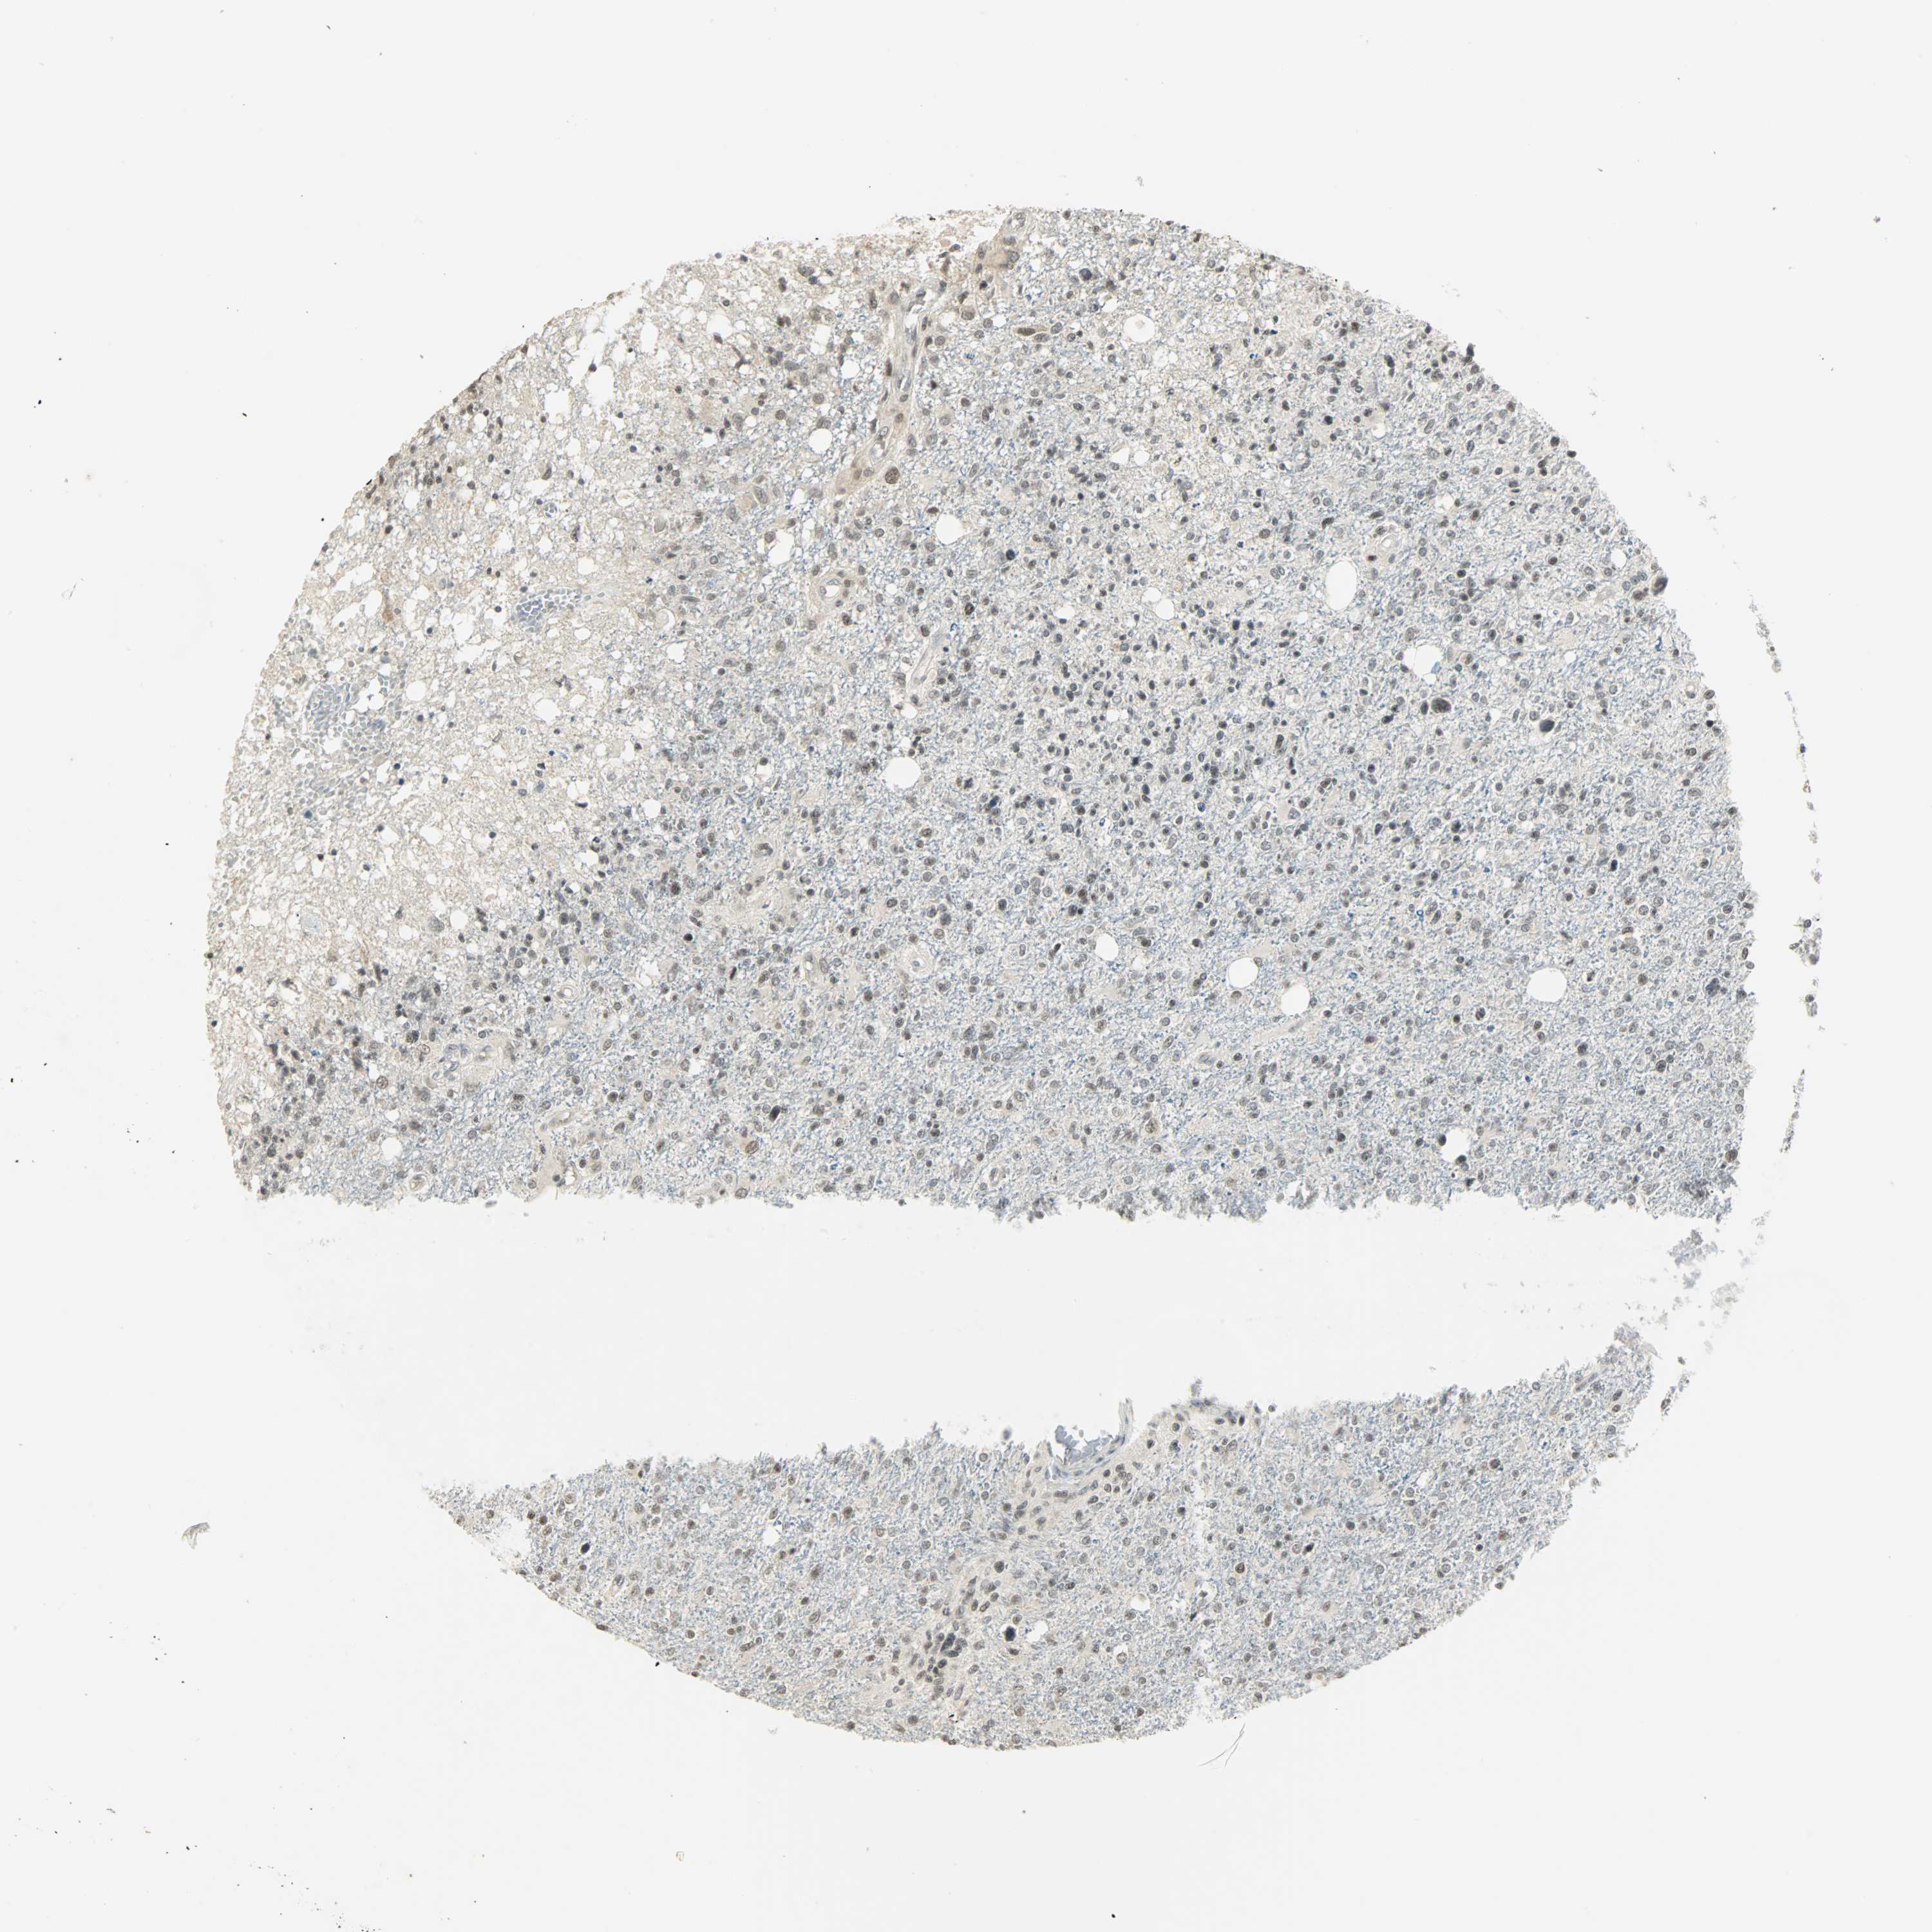

GLIOMA - Protein expressioni

A mouse-over function shows sample information and annotation data. Click on an image to view it in a full screen mode. Samples can be filtered based on level of antibody staining by selecting one or several of the following categories: high, medium, low and not detected. The assay and annotation is described here.

Note that samples used for immunohistochemistry by the Human Protein Atlas do not correspond to samples in the TCGA dataset.

Antibody stainingi

Antibody staining in the annotated cell types in the current human tissue is reported as not detected, low, medium, or high, based on conventional immunohistochemistry profiling in selected tissues. This score is based on the combination of the staining intensity and fraction of stained cells.

Each image is clickable and will lead to virtual microscopy that enables deeper exploration of all samples and also displays staining intensity scores, fraction scores and subcellular localization as well as patient and tissue information for each sample.

Antibody HPA008751

Antibody CAB005227

Staining

High

Medium

Low

Not detected

Intensity

Strong

Moderate

Weak

Negative

Quantity

>75%

75%-25%

<25%

None

Location

Nuclear

Cytoplasmic/membranous

Cytoplasmic/membranous,nuclear

Glioma, malignant, High grade

Glioma, malignant, Low grade

Glioma, malignant, NOS